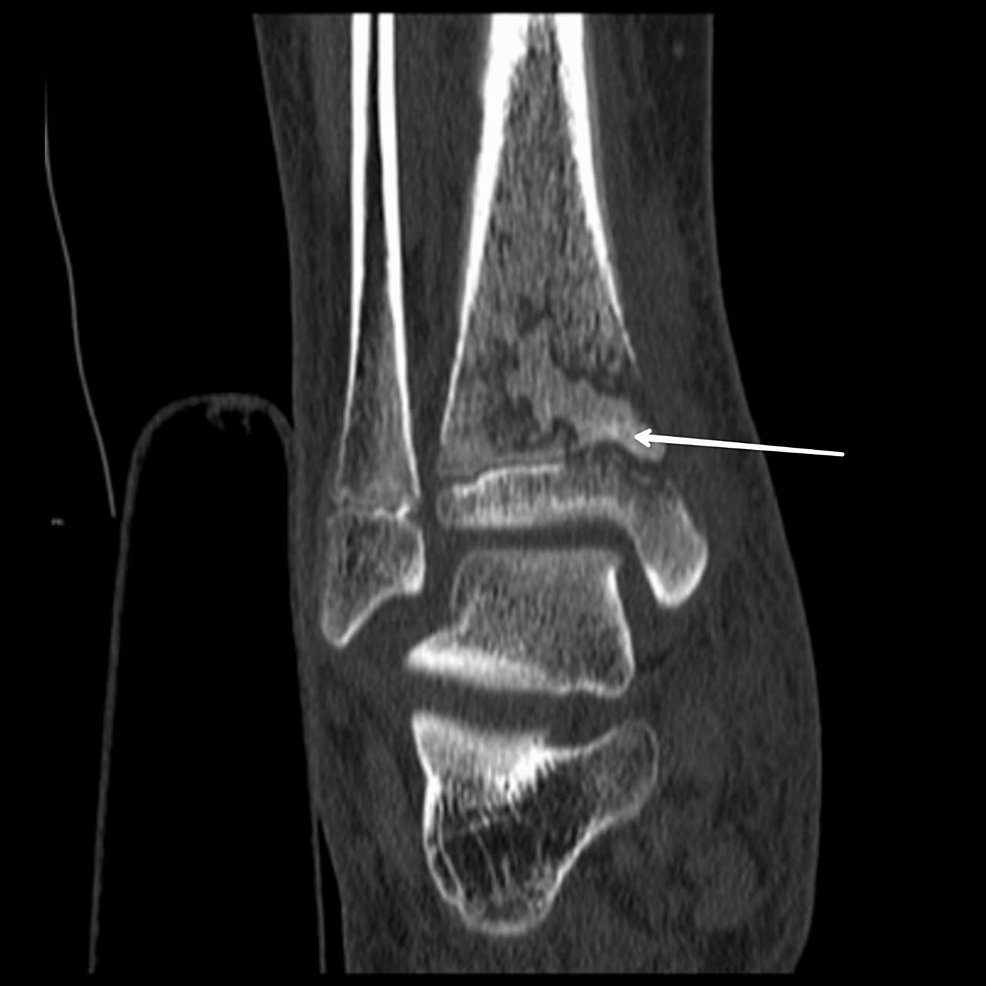

From radiopaedia.org

Chronic recurrent multifocal osteomyelitis Image Osteomyelitis Levofloxacin Treatment of osteomyelitis may include both surgical management and antimicrobial therapy. Symptoms of acute osteomyelitis include pain,. General issues related to treatment of. In this narrative review, we aim to provide a comprehensive overview of the existing evidence on three important aspects of systemic antimicrobial. It may be acute or chronic. Osteomyelitis is an inflammatory condition of bone secondary to. Osteomyelitis Levofloxacin.